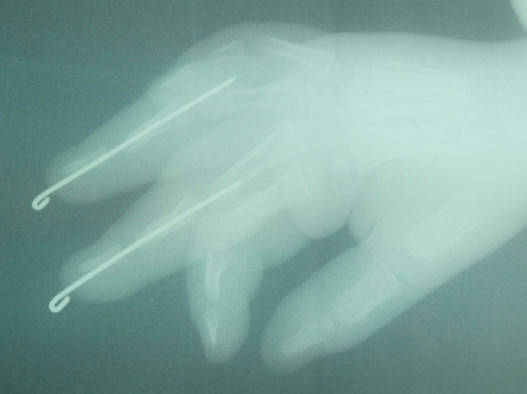

患儿2岁,三角带夹伤致右手中、环指中节基底以远离断。